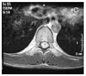

Enhanced axial MR imaging of the schwannoma

MRI是诊断椎管内占位病变的有效手段,因而不难区分髓内和髓外肿瘤,但髓内神经鞘瘤却没有特异性征象。目前,有关髓内神经鞘瘤影像学表现的报道较少,而且部分病例的MRI资料不全,多数学者认为髓内神经鞘瘤具有髓外硬膜内神经鞘瘤相似的影像学表现。一般来说,髓内神经鞘瘤MRI表现为T1WI等或稍低信号,T2WI等或稍高信号,多与脊髓界限清晰,可伴有脊髓空洞、水肿或囊变,注药增强扫描后可见肿瘤实质明显均匀强化且边界清晰[10]。本例肿瘤实质为稍低T1、高T2信号,其内可见明显的囊变区,增强后肿瘤实质部分强化明显均匀,边界清楚,且继发有脊髓空洞,这些表现虽与神经鞘瘤的典型征象相一致,但由于髓内神经鞘瘤发病率极低,故容易导致误诊。因此,结合此次诊疗经验,当MRI检查显示髓内病变显著强化、边界光滑清晰时应想到神经鞘瘤的可能。钱银峰等[11]总结以下征象有助于神经鞘瘤的诊断:(1)肿块以等或稍长T1、等或长T2信号为主,常伴有囊变;(2)增强后实质部分明显强化,且强化较均匀;(3)增强后肿瘤边界消楚;(4)肿瘤多较小,常不超过3个椎体节段;(5)肿瘤相连髓外神经根增粗(具有特征性,但较少见)。Kim等[12]认为瘤周水肿轻微是其特征之一。本组瘤周水肿较轻微,符合其特征性表现,但本组患者肿瘤较大,跨位T9~L1,提示肿瘤大小无明显诊断特异性。